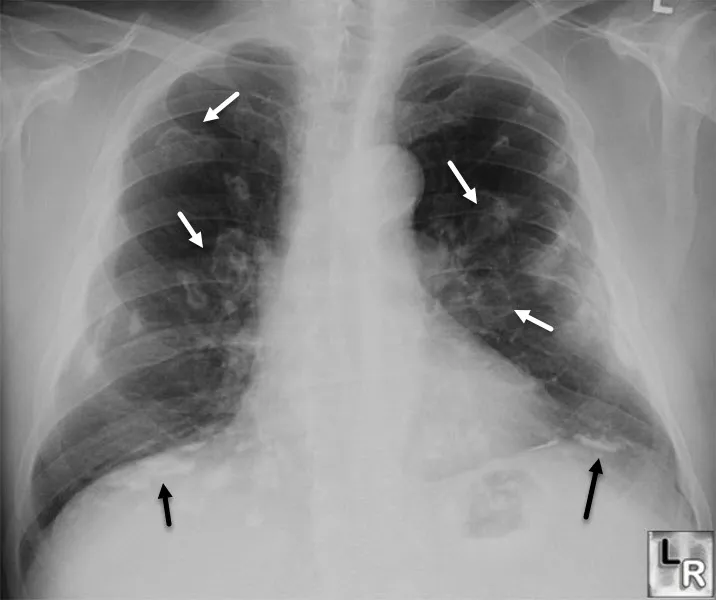

- Chest X-ray (upper lobe infiltrates, cavitation, lymphadenopathy)

| Chest X-ray | Abnormal | Normal |